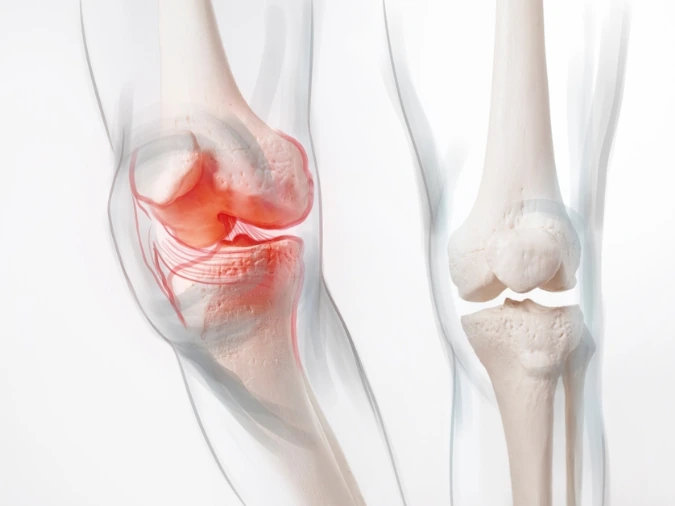

Il ginocchio è un’articolazione complessa e fondamentale per la stabilità, il cammino e l’equilibrio dell’intero arto inferiore. Quando le superfici articolari sono gravemente danneggiate e non rispondono più alle terapie conservative, la sostituzione protesica può diventare la soluzione più efficace per recuperare mobilità e autonomia.

La causa più comune che porta alla necessità di impianto di protesi è l’artrosi.

Si tratta di una degenerazione progressiva della cartilagine articolare, che rende sempre più difficile compiere anche i movimenti più semplici, come piegare il ginocchio o alzarsi da una sedia. Il dolore tende a diventare continuo, spesso presente anche a riposo, e si associa a rigidità e gonfiore.

Oltre all’artrosi primaria, spesso legata all’invecchiamento, esistono forme secondarie che richiedono altrettanta attenzione. Tra queste, l’artrite reumatoide è una delle più note: si tratta di una condizione infiammatoria cronica che può causare gravi danni alla struttura articolare. Anche i postumi di fratture, lesioni articolari trascurate o traumi importanti possono accelerare la degenerazione e portare a una situazione simile.Altre situazioni più rare, ma altrettanto significative, includono l’osteonecrosi e le deformità strutturate dell’arto inferiore, come il ginocchio valgo o varo marcato, che alterano l’equilibrio meccanico e aumentano l’usura su un solo compartimento dell’articolazione.